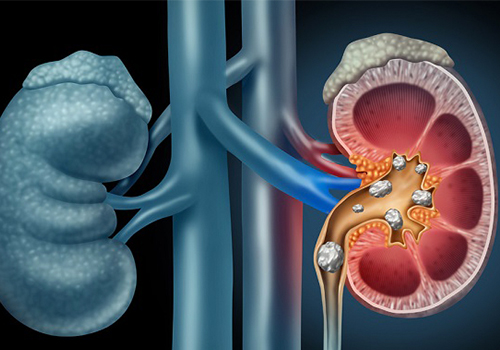

![]() Sỏi thận và các dị vật đường tiết niệu: Sự xuất hiện của sỏi hoặc một số dị vật cọ xát gây kích thích cổ bàng quang nên có hiện tượng tiểu nhiều lần. Biểu hiện lâm sàng của sỏi thận rất đa dạng, trong đó có triệu chứng tiểu đêm đi kèm là tiểu khó, nước tiểu ít, tiểu buốt, đau lưng và có thể có máu trong nước tiểu… những bệnh nhân bị sỏi thận nếu không chữa trị sớm và kịp thời thì sẽ có nguy cơ bị suy thận.

Sỏi thận và các dị vật đường tiết niệu: Sự xuất hiện của sỏi hoặc một số dị vật cọ xát gây kích thích cổ bàng quang nên có hiện tượng tiểu nhiều lần. Biểu hiện lâm sàng của sỏi thận rất đa dạng, trong đó có triệu chứng tiểu đêm đi kèm là tiểu khó, nước tiểu ít, tiểu buốt, đau lưng và có thể có máu trong nước tiểu… những bệnh nhân bị sỏi thận nếu không chữa trị sớm và kịp thời thì sẽ có nguy cơ bị suy thận.